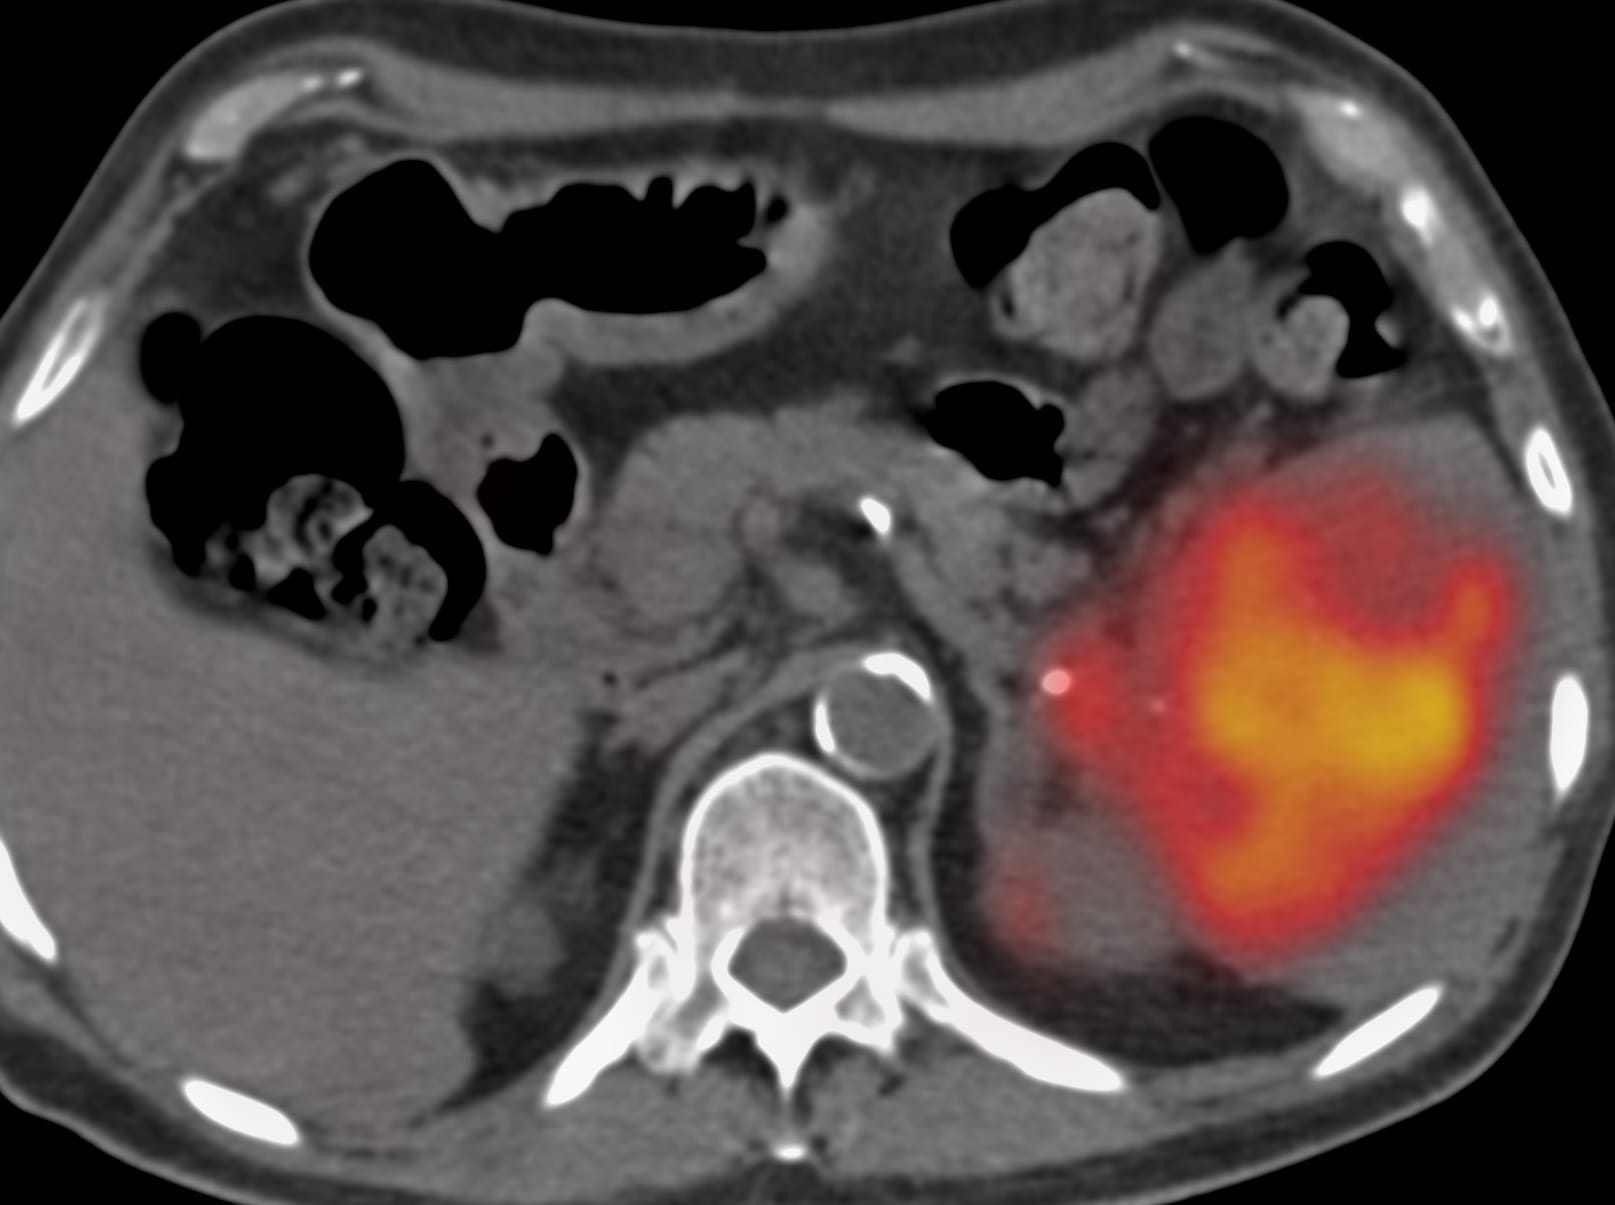

66-years old man presented with a mass in the spleen involving the tail of the pancreas.

Findings: Large splenic mass involving tail of pancreas

Lesion Biopsied: Splenic mass

Diagnosis: Non-Hodgkin’s lymphoma, large B-cell type